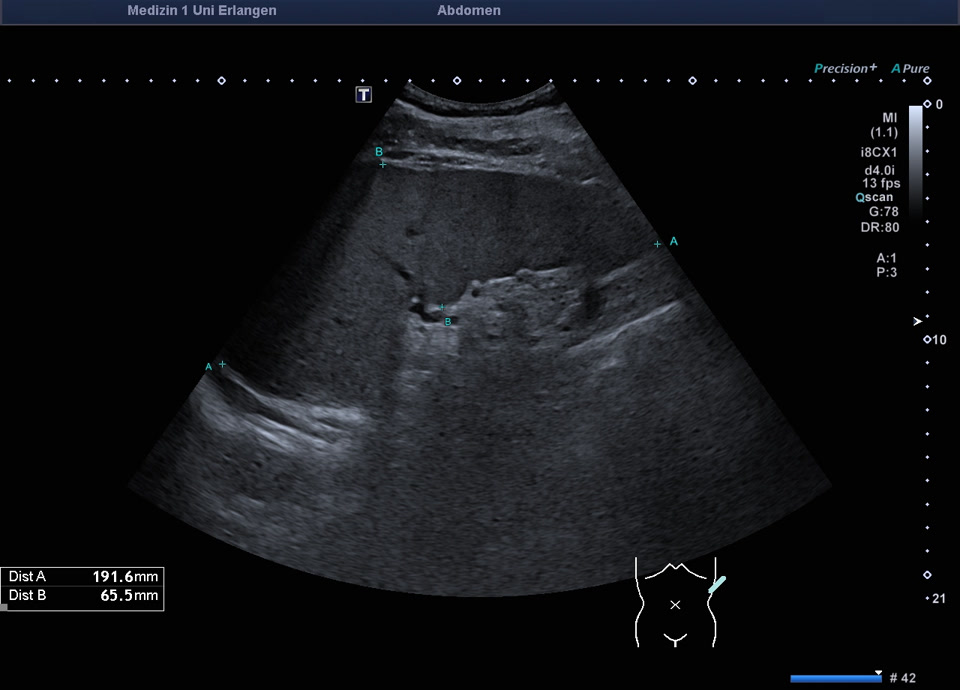

Splenomegalie

Regrediente Splenomegalie bei Z.n. Milzarterienverschluss (Verlauf folgt im nächsten Bild)

Regrediente Splenomegalie bei Z.n. Milzarterienverschluss